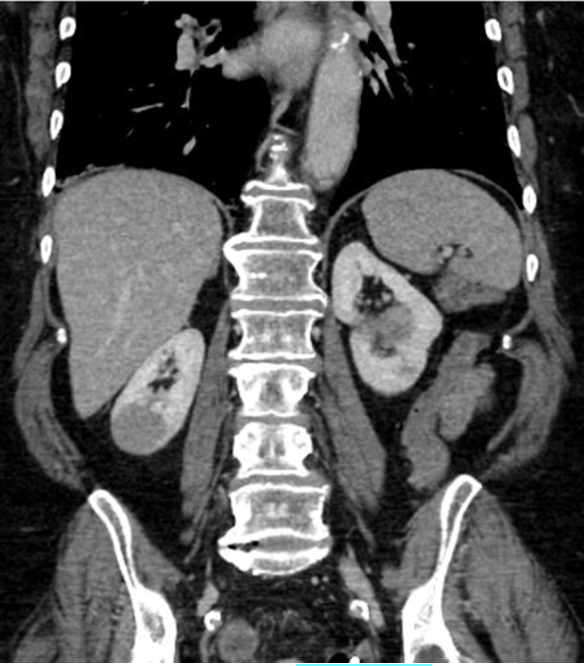

Q

Hvilken CT-projektion er vist?

A

• Coronal